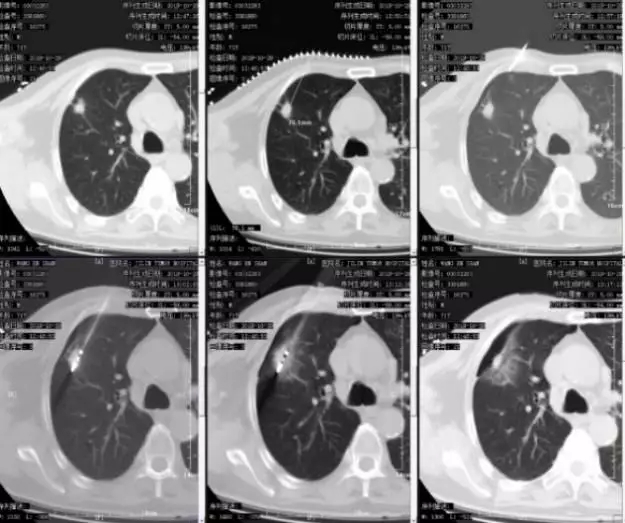

1周后CT复查发现,PET-CT显示有活性的病灶周围,出现1-1.5cm的完整消融环,提示达到了肿瘤活性完全消融的目的。患者目前已出院,病情仍在随访中。

图十:2019.11.4复查CT:病灶周围出现1-1.5cm的消融环。